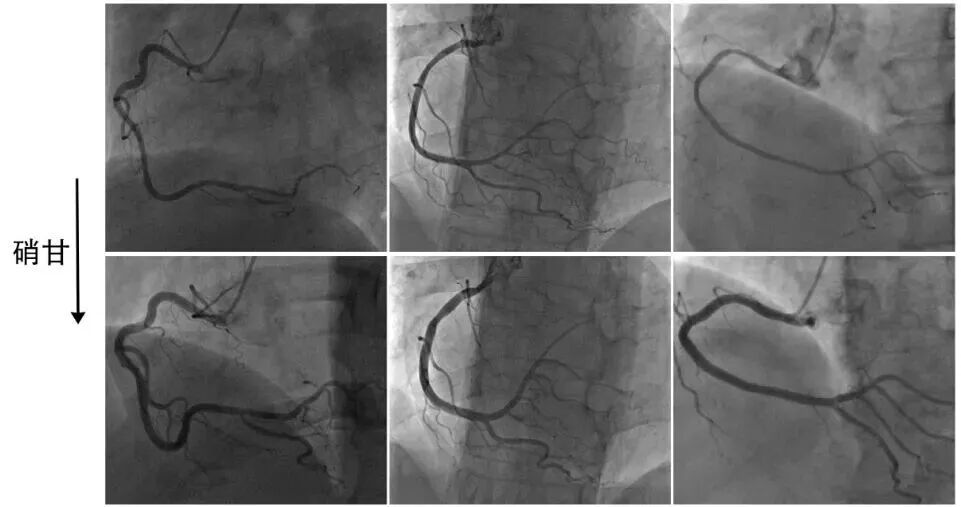

1、细长冠脉

冠脉从开口到远段匀称性细长,类似于扩心病或瓣膜病等扩大心脏的“被纵向拉伸”的冠脉,可以称之为苗条型、瘦长型、模特型冠脉。容易误诊为正常冠脉!

造影一旦发现近段和远段血管直径相仿甚至更小,或冠脉主干直径接近造影导管时,要高度怀疑冠脉痉挛的可能性(图1-2)。注意其特点是细而长!并非细小。

图1 右冠痉挛表现为冠脉细长

图2 左冠痉挛表现为冠脉细长